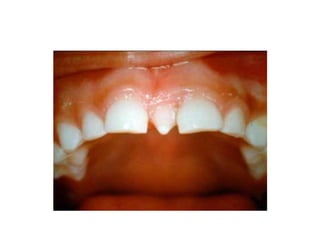

6. Fusion

Merupakan hasil dari penggabungan dua

benih gigi bersebelahan yang sedang

berkembang.

8. Gemination

Merupakan anomali yang terjadi ketika satu

tooth bud berusaha untuk membelah.